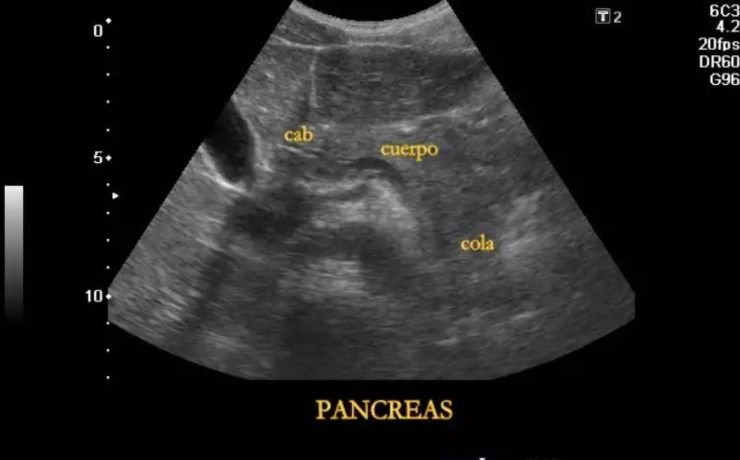

EL MODO A (modo de amplitud) fue el primer método utilizado para formar imágenes de ultrasonido. EL MODO B: modo de brillantez MODO M: modo de movimiento. Tiene su utilidad principal en ecocardiografía tanto en la fetal como en la del adulto. MODO B.- imagen en tiempo real. Al mover